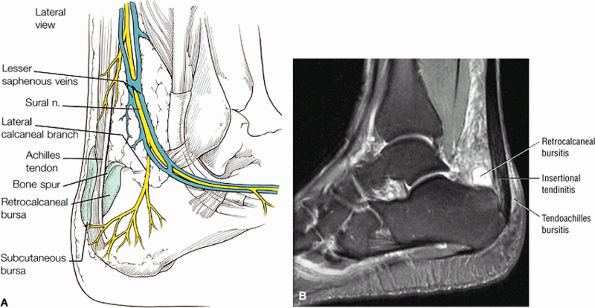

Enthesopathic insertional tendinitis (Fig. 5.114)

Haglund's deformity (Figs. 5.115, 5.116, and 5.117) (insertional tendinitis with reactive calcaneal marrow edema [see Fig. 5.116], and the constellation of thickened tendon, retrocalcaneal/tendo Achilles bursitis, and a calcaneal bony prominence)

Haglund's deformity represents insertional tendinitis with a posterosuperior calcaneal bony prominence and retrocalcaneal tendo Achilles bursitis.